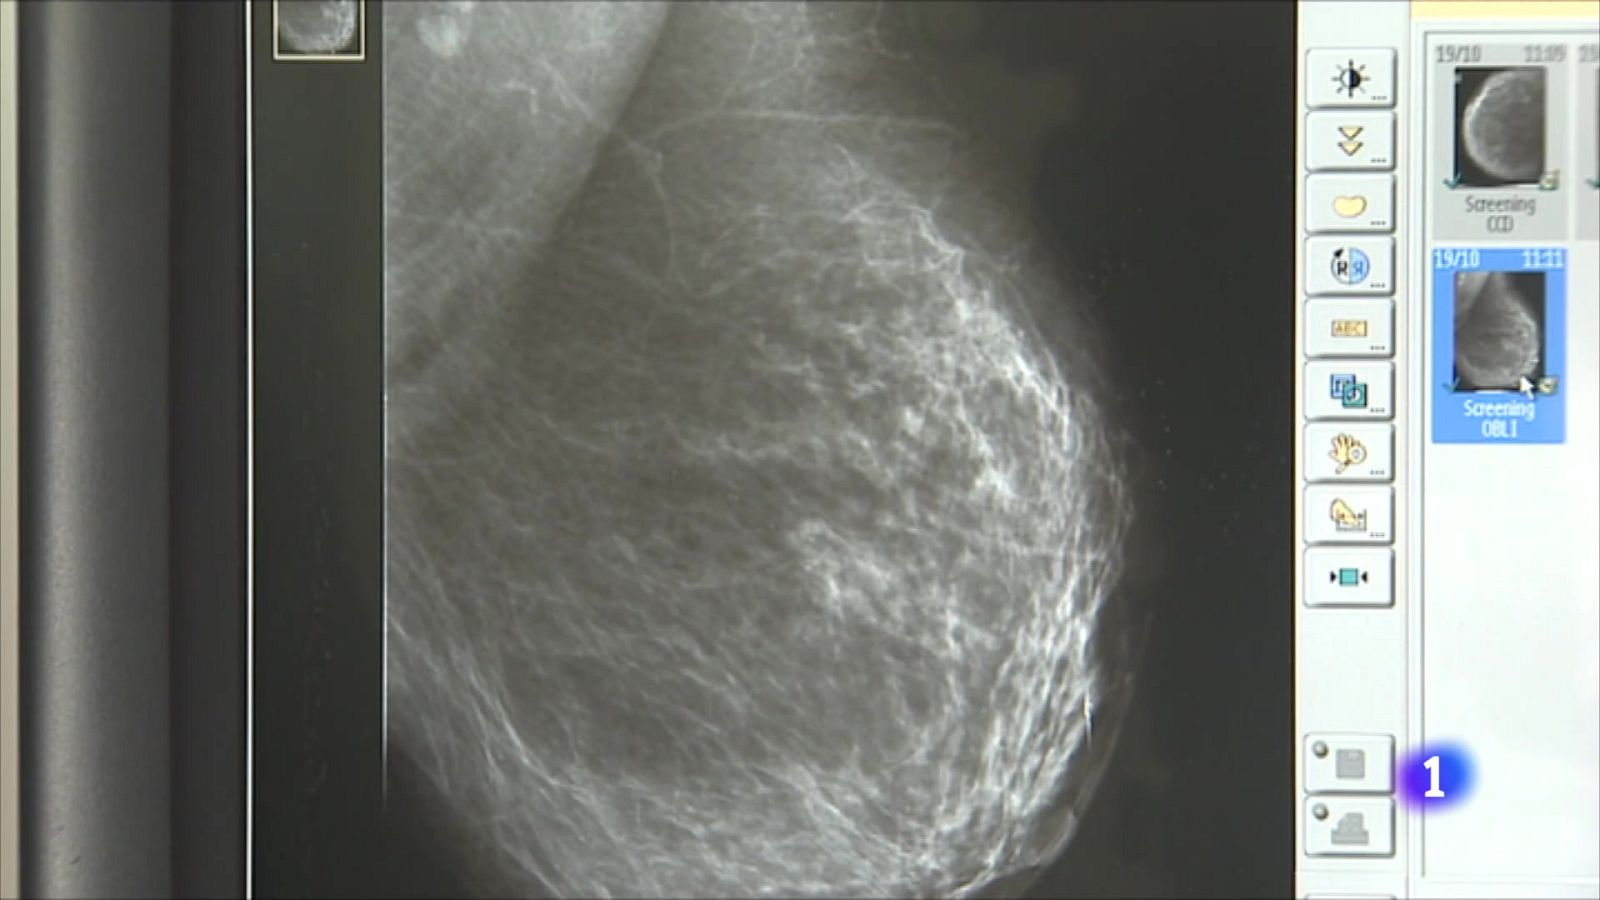

-La prevalència mitjana del càncer de mama és de quasi 16.500 casos a la Comunitat Valenciana. Gràcies al diagnòstic preçoç i a la millora dels tractaments, s'ha aconseguit una supervivència del 85% als 5 anys.